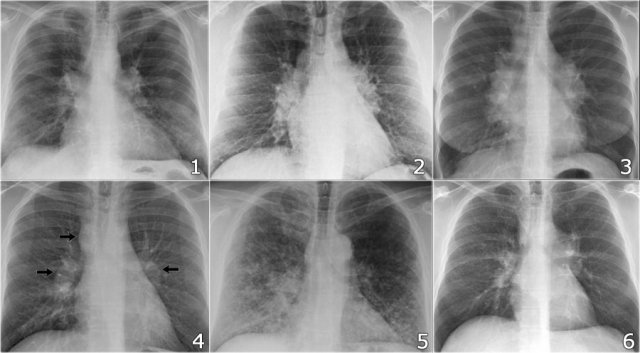

Here some more examples of sarcoidosis.

Click to enlarge.

- Lymphadenopathy and groundglass appearance of the lungs

- Lymphadenopathy, 1-2-3 sign

- Bulky lymphadenopathy

- 1-2-3 sign

- Nodular lung pattern, no lymphadenopathy

- Hilar and paratracheal lymphadenopathy